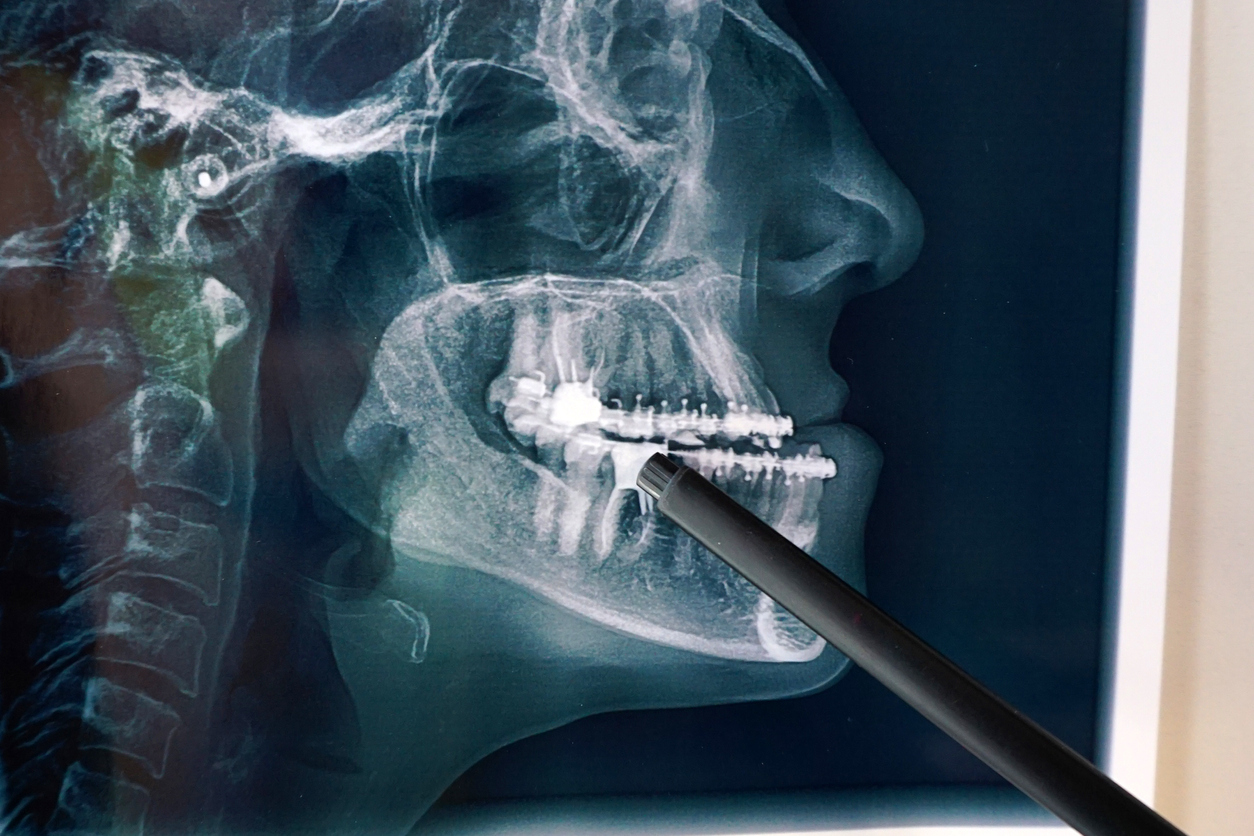

Oral and maxillofacial surgery is a surgical specialty that treats complex conditions of the mouth, teeth, jaws and facial tissues. These procedures include the correction of facial malformations, complex extractions, treatments for jaw problems, facial fractures, among others. This specialty is designed to improve both the functional and aesthetic health of the mouth and face.

Based on the diagnosis, we design a surgical plan that is tailored to your situation. This may include advanced techniques such as orthognathic surgery, cyst removal, or treatment of facial fractures.

The surgery is performed under local or general anesthesia, depending on the type of procedure. Our specialists use state-of-the-art technology to ensure maximum precision.